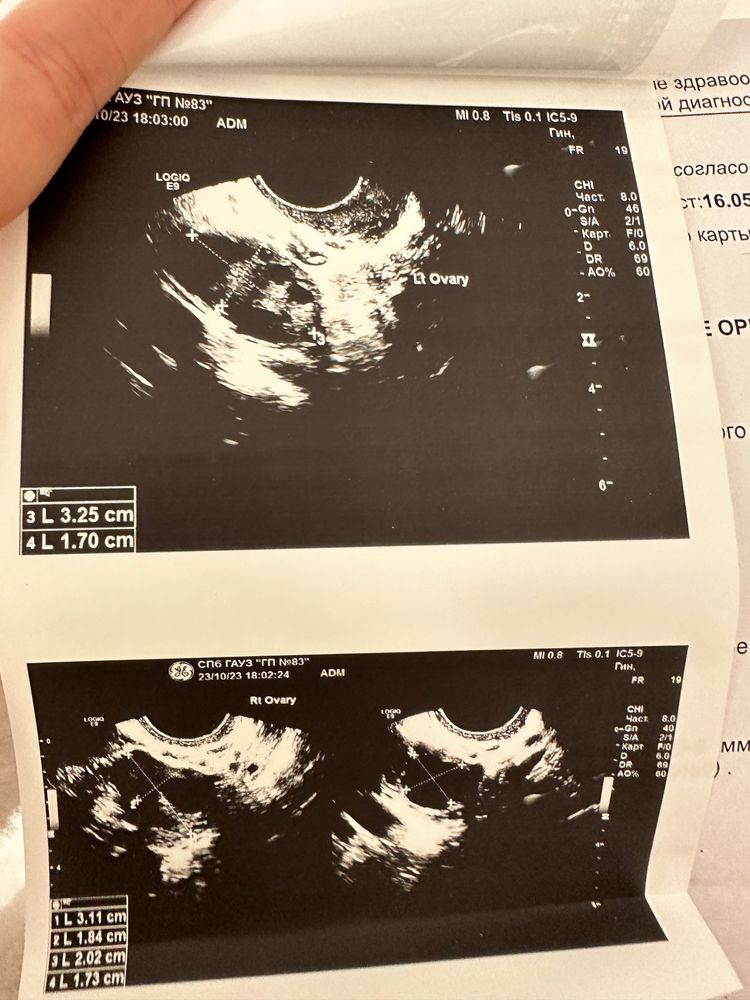

Тест отрицательный- беременности нет. На узи кисты яичников

У вас на фотографиях яичники